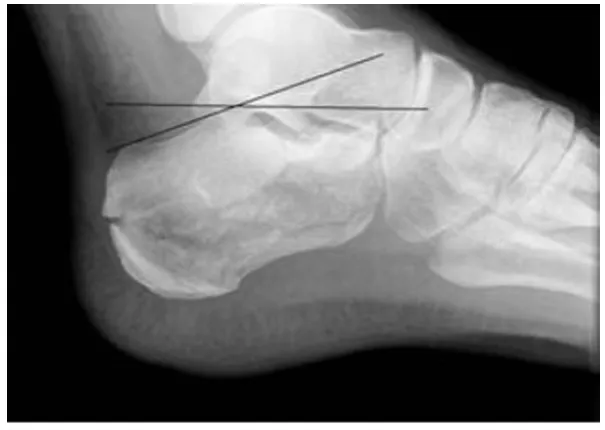

The Boehler angle

Post. articular surface의 highest point(B)와 Ant. process의 highest point(C)를 잇는 선

Post. articular surface의 highest point(B)와 Calcaneal tuberosity의 most sup. part(A)를

→ ⓧ과 ⓨ가 만나는 각도가 25~40°가 정상. 이 각이 25° 이하면 골절을 의심해야 한다.